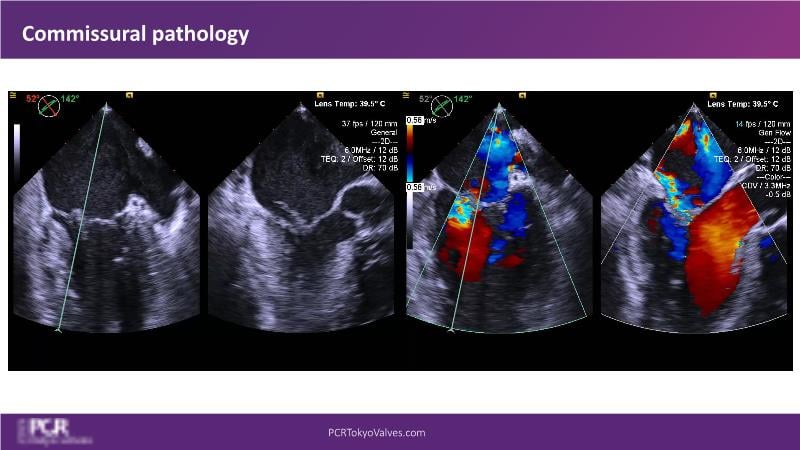

Watch this session to get an overview of a new TEER device, follow the step-by-step procedure related to initial experiences with this device for a Japanese patient with degenerative mitral regurgitation, learn about the latest data from RCT and registries, and follow discussions of challenging TEER cases!

- To understand how novel TEER device provides new possibilities in TEER

- To learn procedural step-by-step of novel device